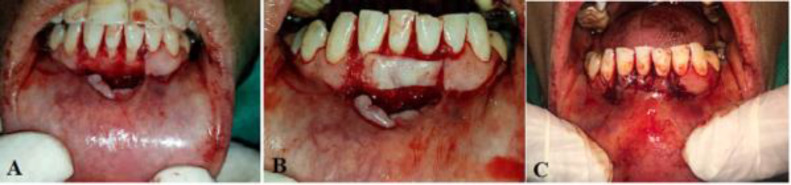

Objectives: The purpose of this study was to compare the clinical performance of coronally advanced flap (CAF) with connective tissue graft (CTG) and vestibular incision subperiosteal tunnel access (VISTA). Materials and Methods: The statistical population of this randomized clinical trial consisted of 24 healthy non-smokers with Miller Class I or II gingival recession (GR) defects, equally divided into two groups of 12 to receive either a CAF or the VISTA technique. Clinical parameters including the clinical attachment level (CAL), gingival biotype, pocket probing depth (PPD), recession height (RH), recession width (RW), root coverage (RC), and keratinized tissue width (KTW) were measured and compared between the two groups using ANCOVA, Fisher's exact test, independent samples t-test, Mann-Whitney U test, and repeated-measures ANOVA (alpha=0.05). Results: The CAF group showed a significantly higher RC percentage (97.22%±9.62%) than the VISTA group (77.22%±24.28%%). Both techniques exhibited similar performance in terms of reducing the PPD and increasing the KTW and gingival attachment. However, the CAF group experienced a significantly greater reduction in CAL, RW, and RH than the VISTA group (P<0.05). Conclusion: The VISTA and CAF groups showed a complete root coverage (CRC) percentage of 33.3% and 91.7%, respectively, indicating higher effectiveness of CAF than VISTA.

Abstract Image